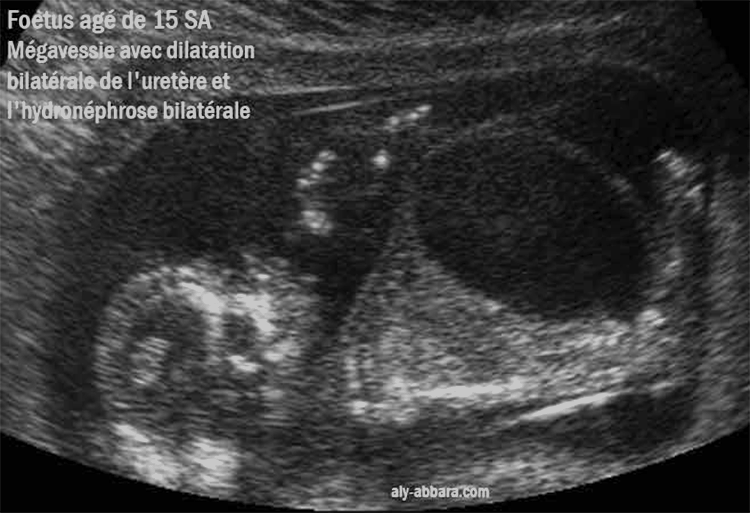

Megavessie importante à 15 SA (Syndrome de Prune Belly)

Mégavessie avec dilatation urétérale, hydronéphrose bilatérales

et paroi abdominale très fine

Fœtus âgé de 15 SA

L'échographie montre une sévère dilatation du l'arbre urinaire : une mégavessie, une dilatation bilatérale des uretères (hydrouretère) et une pyélectasie bilatérale ; la totalité de l'uretère est dilatée sans pouvoir mettre en évidence d'un point d'obstruction.

La dissociation entre l'importante de la distension de la vessie et des uretères puis la dilatation rénale et pyélocalicielle modérée est en faveur avec le syndrome de prune belly.